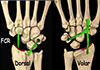

Figure 3 Scaphoidectomy and midcarpal tenodesis with the FCR transosseous T technique. (schematic). Source: Dr. Emmanouil Apergis. |

The transosseous FCR “T-technique” tenodesis was also performed using a volar harvest of a distally based FCR tendon strip, but differed in its method of fixation. Consistent with previously described osseous-anchorage variations of FCR tenodesis [10, 13], a transosseous tunnel was created through the triquetrum from volar to dorsal, enabling the tendon to be delivered dorsally through bone. The free tendon end was then redirected proximally and anchored to the dorsal distal radius, producing a rigid “T-shaped” construct with strong mechanical stability. This technique was chosen when more robust correction of midcarpal malalignment was required compared with ligamentous methods.